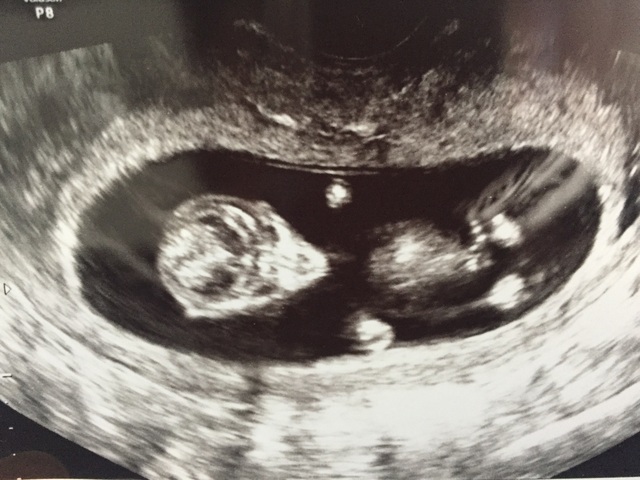

12週6日(12w6d・性別不明・双子)|ちびのすけ さん(37歳)

エコー写真撮影時のエピソード:

およそ1ヶ月前に双子と診断されて初めは戸惑って不安に陥ったけど、今はパパと息子とツインズが生まれて来てくれるのを心待ちにしています。

両親は思いもよらない報告にびっくりしてますが、まずは無事に産まれてきてくれることを願ってくれてます。